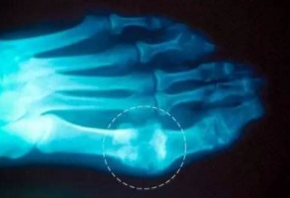

痛风

痛风 ①晚期 ②并发症 病史:12年+

治疗后手指关节、脚趾关节痛风石完全清除,血尿酸降至正常水平,手脚各关节痛感消失,关节活动恢复到正常状态。 ??